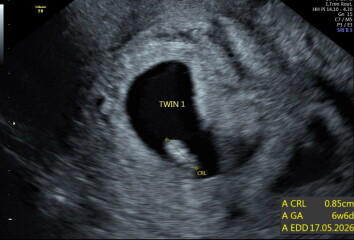

Hey OP, sorry you've not had a response to this yet! Hard to say, really. I learned I was having twins at my 6wk scan - Twin A was measuring 6w6d and Twin B was 6w3d. Here are some pics from my scan which may help you to compare against. You can see B's sac is quite a bit smaller.